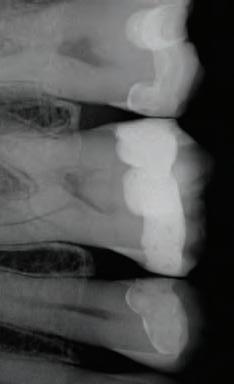

DISTO-OCCLUSAL CLINICAL CASE